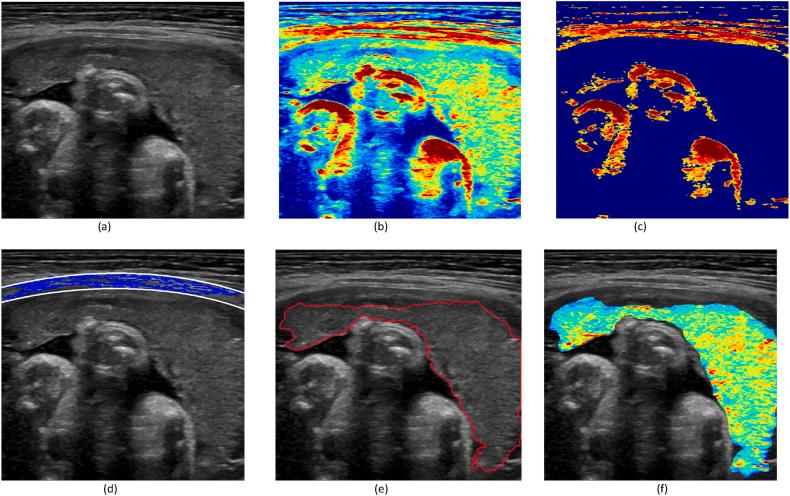

The placenta is a fundamental organ throughout the pregnancy and the fetus' health is closely related to its proper function. Because of the importance of the placenta, any suspicious placental conditions require ultrasound image investigation. We propose an automated method for processing fetal ultrasonography images to identify placental abruption using machine learning methods in this paper. The placental imaging characteristics are used as the semantic identifiers of the region of the placenta compared with the amniotic fluid and hard organs. The quantitative feature extraction is applied to the automatically identified placental regions to assign a vector of optical features to each ultrasonographic image. In the first classification step, two methods of kernel-based Support Vector Machine (SVM) and decision tree Ensemble classifier are elaborated and compared for identification of the abruption cases and controls. The Recursive Feature Elimination (RFE) is applied for optimizing the feature vector elements for the best performance of each classifier. In the second step, the deep learning classifiers of multi-path ResNet-50 and Inception-V3 are used in combination with RFE. The resulting performances of the algorithms are compared together to reveal the best classification method for the identification of the abruption status. The best results were achieved for optimized ResNet-50 with an accuracy of 82.88% ± SD 1.42% in the identification of placental abruption on the testing dataset. These results show it is possible to construct an automated analysis method with affordable performance for the detection of placental abruption based on ultrasound images.

胎盘是整个孕期的一个重要器官,胎儿的健康与胎盘的正常功能密切相关。由于胎盘的重要性,任何可疑的胎盘状况都需要进行超声图像检查。在本文中,我们提出了一种利用机器学习方法处理胎儿超声图像以识别胎盘早剥的自动化方法。与羊水和硬器官相比,胎盘的成像特征被用作胎盘区域的语义标识符。将定量特征提取应用于自动识别的胎盘区域,为每个超声图像分配一个光学特征向量。在第一个分类步骤中,详细阐述并比较了基于核的支持向量机(SVM)和决策树集成分类器这两种方法,用于识别早剥病例和对照。应用递归特征消除(RFE)来优化特征向量元素,以实现每个分类器的最佳性能。在第二步中,将多路径ResNet - 50和Inception - V3的深度学习分类器与RFE结合使用。将算法的最终性能进行比较,以揭示识别早剥状态的最佳分类方法。在测试数据集上识别胎盘早剥时,优化后的ResNet - 50取得了最佳结果,准确率为82.88%±标准差1.42%。这些结果表明,基于超声图像构建一种性能可承受的胎盘早剥检测自动化分析方法是可能的。